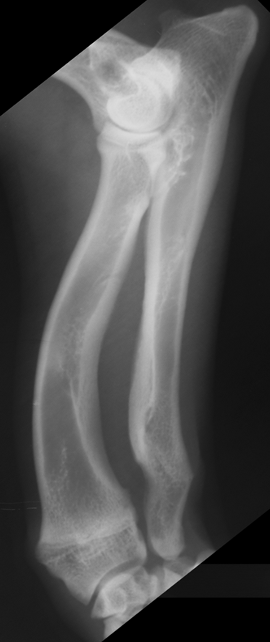

What is shown in these radiographs?

hypertrophic nonunion

-widening of fracture gap

-excessive, non-bridging callus

-sclerotic fracture ends